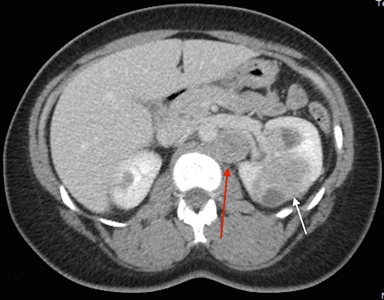

The symptoms of RCC may include hematuria, lower back pain, and a palpable mass. However, a large number of individuals with RCC are asymptomatic. Furthermore, not all individuals with HLRCC present with or develop RCC. Most RCCs are unilateral and solitary; in a few individuals, they are multifocal. The exact incidence of RCC in affected individuals remains to be determined, and widely varying estimates have been provided by different groups (1%–60%).[1,3,8] The incidence appears to vary on the basis of where the study was performed, the referral patterns of individual groups, and the extent to which individuals were screened for RCC. In studies from the National Cancer Institute (NCI), RCC was identified in approximately 32% of families evaluated.[1,3] The median age at detection of RCC was 37 years,[9] although some cases have been reported to occur as early as age 10 years.[10] Another large series of 135 patients estimated that the lifetime risk was 20.8% by age 85 years.[11] In contrast to other hereditary RCC syndromes, RCCs associated with HLRCC are aggressive,[12,13] with a Fuhrman nuclear grade of 3 or 4 in many cases and 9 of 13 individuals dying from metastatic disease within 5 years of diagnosis.[3]Figure 1 depicts RCCs in a patient with HLRCC.

Figure 1. Hereditary leiomyomatosis and renal cell cancer–associated renal tumors are commonly unilateral and solitary; in a few individuals, they are multifocal. Red arrow indicates a retroperitoneal lymph node. White arrow indicates a left renal mass.